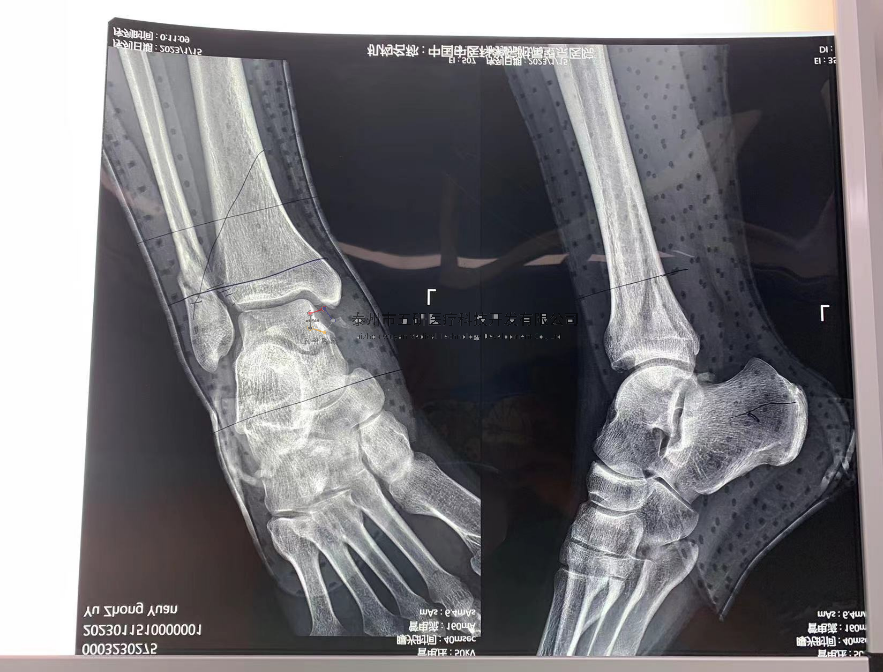

【基本資料】患者,男,41歲

本病例踝關(guān)節(jié)骨折。手術(shù)名稱(chēng):左踝關(guān)節(jié)骨折外固定支架手術(shù)

【治療前影像】

4.png

5.png